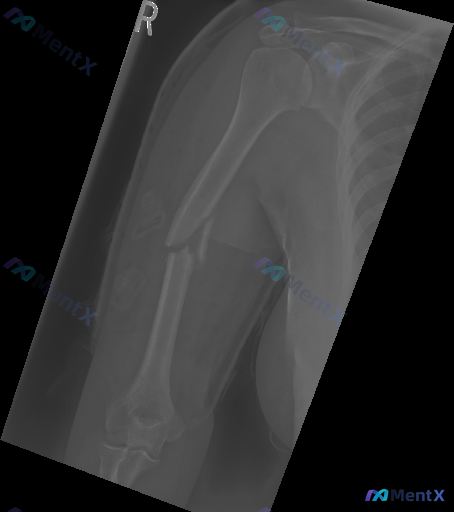

整理到一张放射影像分析资料,是右侧上臂的正位X光片。 先不说结论,只看影像描述里的这些点: - 肱骨干中段骨皮质中断,骨折线清晰,有游离碎骨片 - 断端有侧方移位和重叠,近端向外、远端向内 - 骨质密度基本正常,没有明显的溶骨/成骨破坏,也没有典型骨膜反应 - 肩关节对位可,部分肘关节结构可见,未见...